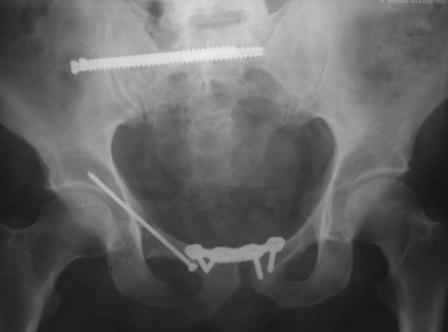

в архиве нашел подобный случай

С Уважением А.Миронов(Новокузнецк)

80% нагрузки берут на себя задние отделы тазового кольца и фиксировав только переднее полуколцо механическую стабильность таза не восстановить. Для этого нужно выполнить остеосинтез задних отделов, в данном случае крестца, судя по Вашему описанию рентгенограмм, подойдет перкутанный остеосинтез S1 через крестцогоподвздошное сочленение позиционным (не стягивающим)канюлированным винтом.И тогда можно спокойно вертикализировать пациента.